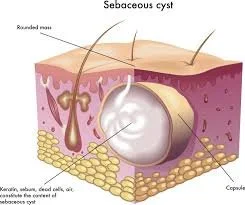

Sebaceous Cysts in Dogs: Causes, Symptoms, Diagnosis, and Treatment

Sebaceous cysts are a common cause of lumps under a dog’s skin. Learn the causes, symptoms, diagnosis, and treatment options from Dr. Roger Hart at Bushnell Animal Clinic.